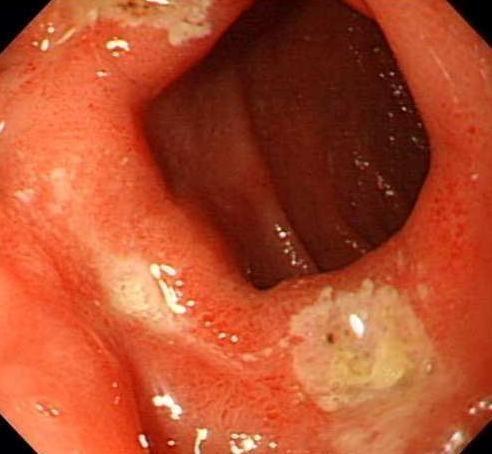

症状一:鼻粘膜溃疡、糜烂常见于鼻中隔前下区(Little区),多由慢性炎症引起。化学性气体、高温、干燥空气皆可成为诱因。此外,鼻中隔棘突或矩状突、鼻中隔穿孔、萎缩性鼻炎,也可引起局部鼻粘膜溃疡形成而导致出血。鼻窦的急性感染。

症状二:肿瘤:肿瘤所致鼻出血多系肿瘤本身表面溃烂引起,出血程度因肿瘤性质而异。恶性肿瘤晚期侵犯大血管时可发生致命性鼻出血。鼻粘膜溃疡会出现一些表面的症状,也会有内在的症状,这些都是可以感受到的。

相关图片